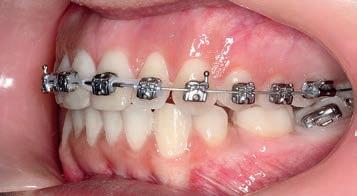

3 months of sagittal correction, the occlusal lock of the Class I platform had been accomplished (Sagittal First) and the case was ready to progress to the next stage. The Motion appliance was removed. While in this case, it would have been easy to finish the case with Invisalign, the patient chose fixed appliances so Carriere SLX .022 PSL brackets were bonded.

Treatment followed the Carriere System archwire sequence:

.014 Cu Nitanium (27 °C)

.014 x .025 Cu Nitanium(27 °C)

.017 x .025 Cu Nitanium (35 °C)

.019 x .025 Cu Nitanium (35 °C)

The first wire, a .014 round Cu Nitanium wire, corrected the rotations of the incisors. With the .014 x .025 Cu Nitanium wire, power chain was used to close the spaces between the incisors. After these spaces closed, the .017 x .025 Cu Nitanium wire would begin torque control with the final archwire, the .019 x .025 Cu Nitanium wire, to finalise the axial angulations of the anteriors. When the upper .019 x .025 archwire was engaged, three links of power chain were run bilaterally from the 2nd premolar to the 1st premolar and from the 1st premolar to a crimpable hook attached to the wire distal to the lateral incisor to retract the anterior segment, bringing it into the final desired position.

Figs. 9a–c: Situation after 1 month of correction with Sagittal First approach. – Figs. 10a–c: Situation after 2 months of correction. – Figs. 11a–c: Situation after 3 months of correction: Class I achieved. – Figs. 12a–c: Situation after 4 months of treatment (3 months of Motion sagittal treatment and 1 month in fixed appliances). .014 x .025 wire with power chain to close the spaces between the incisors. – Figs 13a–c: Situation after 7 months of treatment (3 months of Motion sagittal treatment and 4 month in fixed appliances). .019 x .025 archwire was engaged with power chain to retract the anterior segment and bring it into the final desired position. – Figs 14a–c: Final situation achieved after 11 months of treatment (3 months of Motion sagittal treatment and 8 months of Carriere SLX fixed appliance therapy).